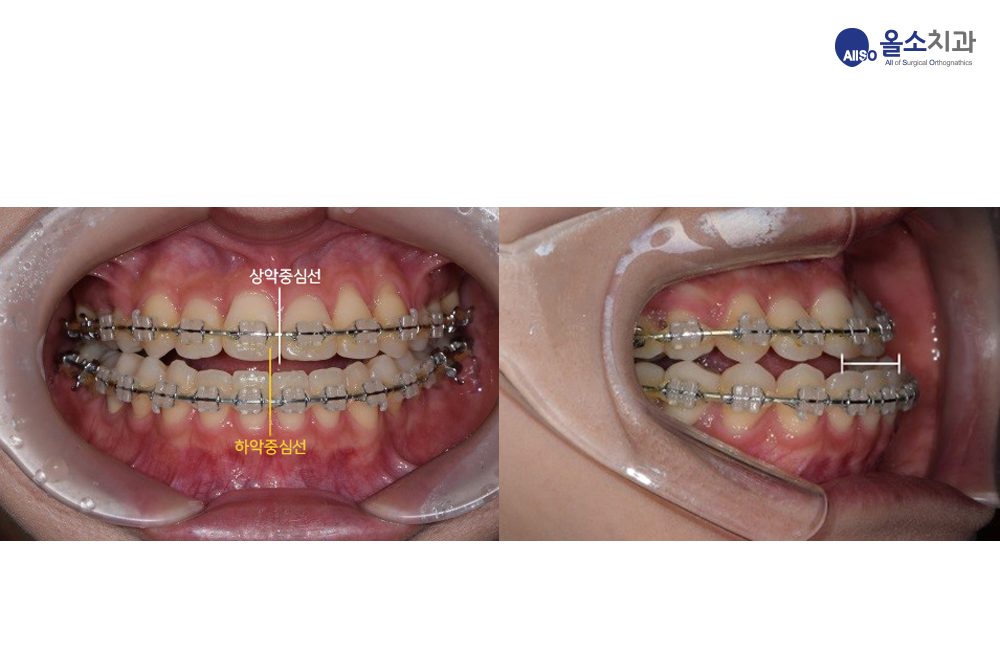

교합의 변화를 수술 전 교합 상태와 비교하여 보겠습니다.

수술 전에는 아래턱이 위턱에 비해 앞으로 나와있는 반대교합으로 위아래 앞니가 맞물리지 않으며, 좌우 비대칭이 심해 가운데 선이 맞지 않았습니다.

정상적인 교합은 1) 윗니-아랫니의 중심선이 맞고 2) 윗니가 아랫니를 살짝 덮어야 합니다. 수술 후 사진에서 술전의 반대교합과 비대칭이 교정된 것을 알 수 있습니다.